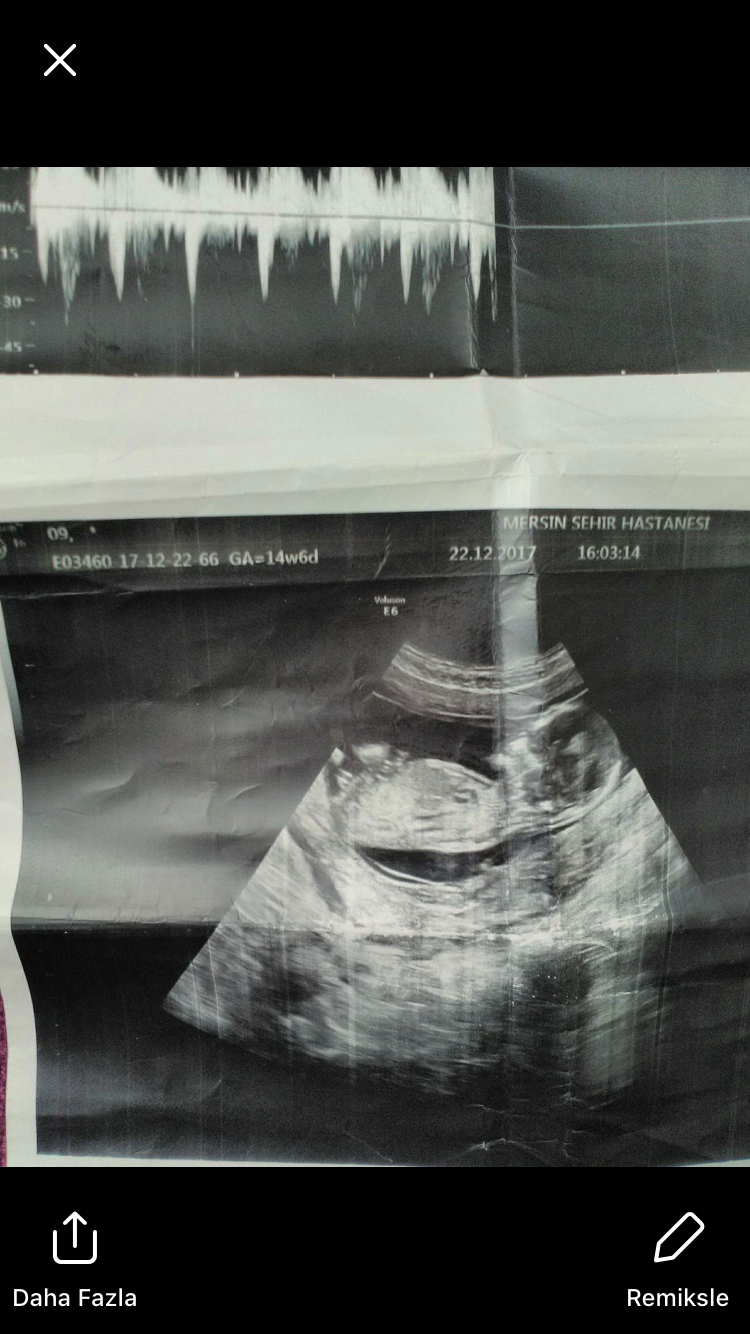

Merhaba bunu yolladı arkadaşım 14 haftalık çok teşekkürler 🙂

Merhaba, çıkıntı tam anlaşılmıyor görsel ışığa fazla maruz kalmış emin olmamakla birlikte bebeğin cinsiyetinin erkek olduğu kanaatindeyim. Yine belirtelim bu haftalarda cinsiyet tahminin de yanılmalar olabilir. 16-17-20 . haftalarda net olarak cinsiyet görülebilir.